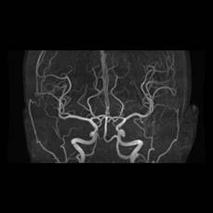

3T MRIを用いた脳ドックも行っています。

脳ドックは、脳の病気を未然に防ぐことを目的とした予防的な検査です。

脳・脳血管・頚部血管を詳しく調べ、

などの有無を確認し脳梗塞やクモ膜下出血を発症する前にリスクを発見できる可能性があります。

自覚症状のない段階での早期発見・予防に役立ちます。